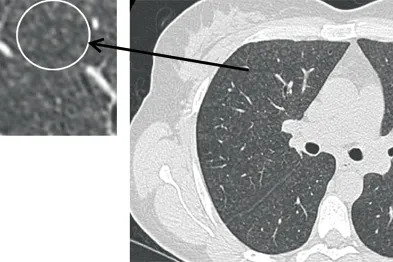

- Diagnosis: CT scan is superior for early detection and detailed assessment; X-ray findings include:

- Upper lobe predominant small, rounded opacities.

- "Eggshell calcification" of hilar lymph nodes (classic).

- Progressive Massive Fibrosis (PMF): opacities >1 cm (general guideline; criteria may vary).